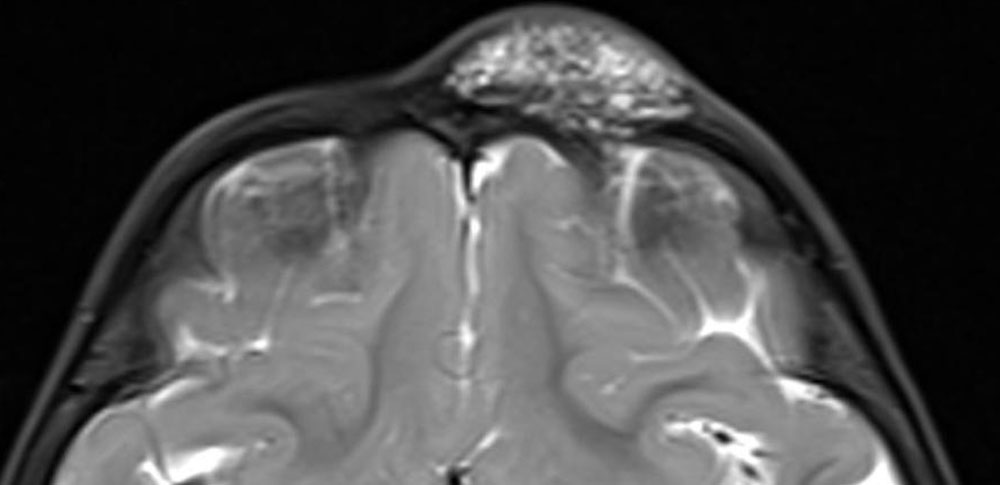

Knowledge of the various stages of development makes it understandable why a circumscribed microcystic or macrocystic lymphatic malformation (hereafter “LM”) develops preferentially in certain areas of the body. A lymphatic malformation is never intracerebral, subglottic, intratracheal or intraarticular, very rarely intraosseous (as in Gorham-Stout syndrome) but occurs all the more frequently in the region of the facial skull and neck, sometimes extending into the mediastinum or from retroperitoneally to the soft tissues of the pelvis and thigh. However, lymphatic malformation can also affect just the skin or the skin and subcutis. This is sometimes in very circumscribed areas measuring only a few centimeters (the term lymphangioma circumscriptum is used clinically for this, although it is not in the ISSVA classification).